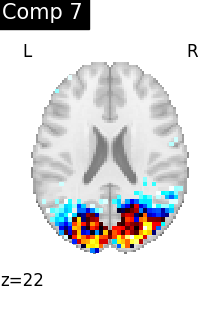

Compare CanICA to dictionary learning¶

Dictionary learning is a sparsity based decomposition method for extracting spatial maps. It extracts maps that are naturally sparse and usually cleaner than ICA. Here, we will compare networks built with CanICA to networks built with Dictionary learning.

For more detailse see Mensch et al.[2].

One plot of each component

for i, cur_img in enumerate(iter_img(dictlearning_components_img)):

plot_stat_map(

cur_img,

display_mode="z",

title=f"Comp {int(i)}",

cut_coords=1,

colorbar=False,

)